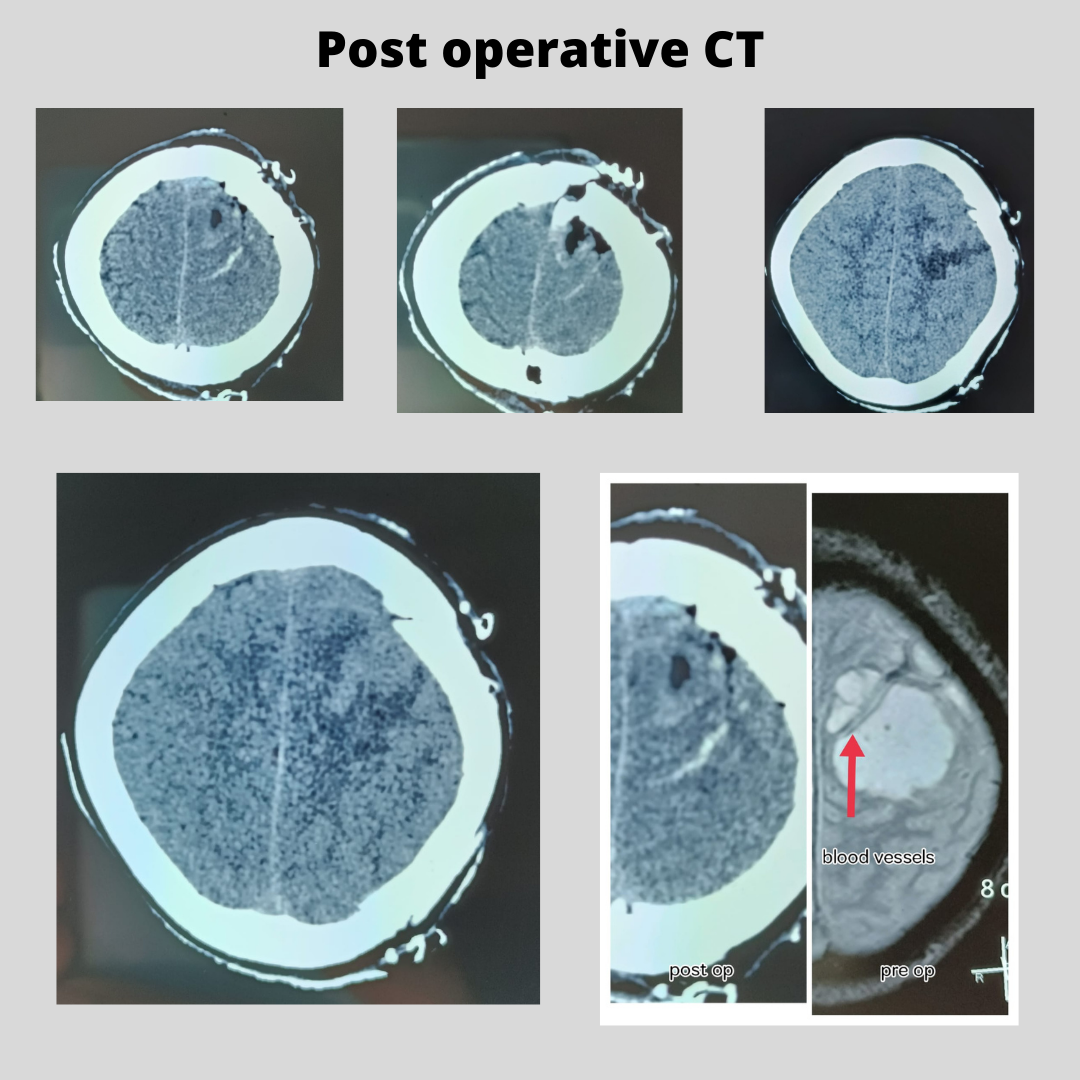

On admission, pt was disoriented with rt hemiplegia. ( Weakness in right limbs)

MRI showed a tumor on the left side of the brain with multiple blood vessels crossing through the tumor.

Yesterday patient underwent surgery and complete excision of the tumor was achieved and all the blood vessels crossing the tumor were preserved.

Today patient is fully conscious and oriented with improvement in the power of the right limbs.